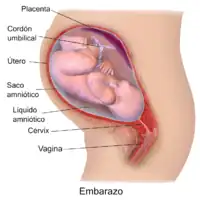

Dentro del útero, el feto está flotando en el líquido amniótico, y a su vez el líquido y el feto están envueltos en el saco amniótico, que está adosado al útero. En el cuello del útero, se forma un tapón de mucosidad densa durante el embarazo para dificultar el ingreso de microorganismos que provoquen infección intrauterina. Este tapón será expulsado durante el inicio del trabajo de parto.

Mientras permanece dentro, el cigoto, embrión o feto obtiene nutrientes y oxígeno y elimina los desechos de su metabolismo a través de la placenta. La placenta está anclada a la pared interna del útero y está unida al feto por el cordón umbilical. La expulsión de la placenta tras el parto se denomina alumbramiento.